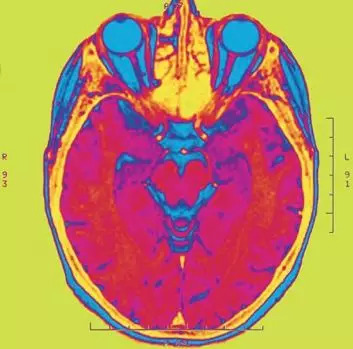

人类的记忆(即使是最珍贵的记忆)是从微观层面开始。妈妈的脸最开始只是你视网膜上的一堆光子,它们向你的视觉皮层发送信号。你听到妈妈声音时,你的听觉皮层把声波转换成电信号。荷尔蒙把体验和环境联系起来:这个人让你感觉很好。这些和其他几乎无数的信息在你的大脑中一闪而过。库库什金说,神经元、相关分子和突触记录了所有这些扰动发生的相对时间。而且,它们把整个体验打包进一个所谓的时间窗口。

显然,记忆不是单独存在的。大脑把体验分解成同时经历的多个时标,比如声音被分解成同时感知的不同频率。这是个嵌套系统,每段记忆存在于长度不同的多个时间窗口内。时间窗口包含记忆的各个部分,比如分子的信息交换。在记忆的层面上,这种信息交换是不可见的。

这对神经学家来说也很难理解。他们还需要很长时间才能弄清楚记忆形成的具体细节。“在理想的世界中,我们可以及时追踪每个神经元的活动,”库库什金说。可是,就目前而言,像人类连接组计划这样的项目虽然代表了相关研究的最前沿,但它们仍然只是研究静止状态下的大脑整体情况。和记忆本身一样,让这个项目转向动态研究完全是时间问题。